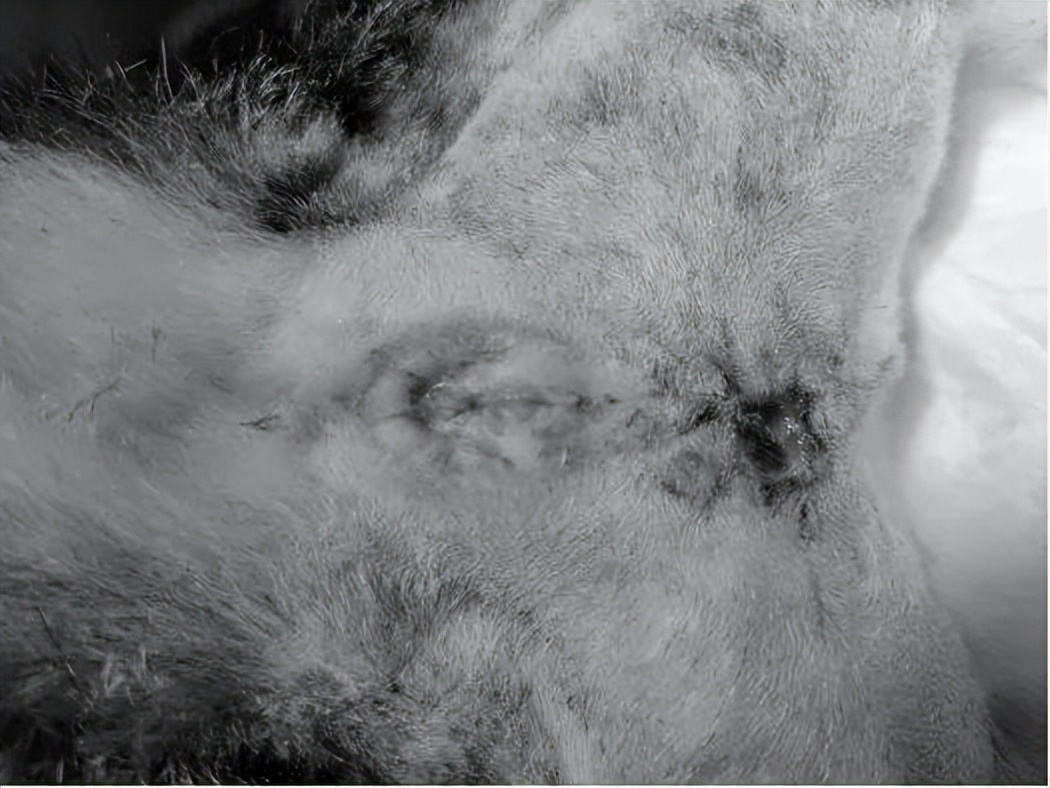

一周后尿道口情况

术后四周尿道口情况